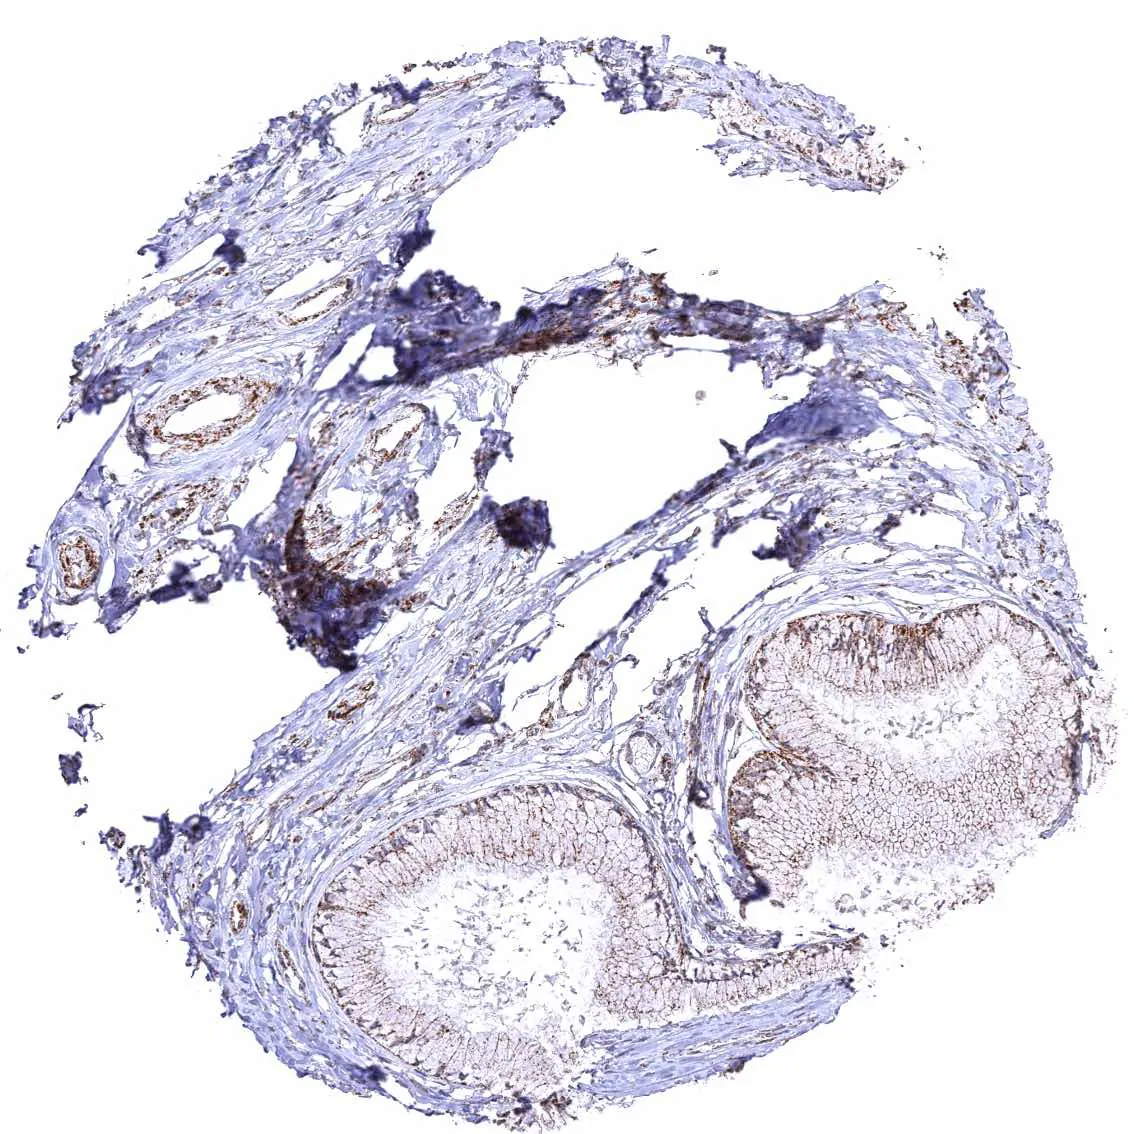

Epididymis (Cauda)